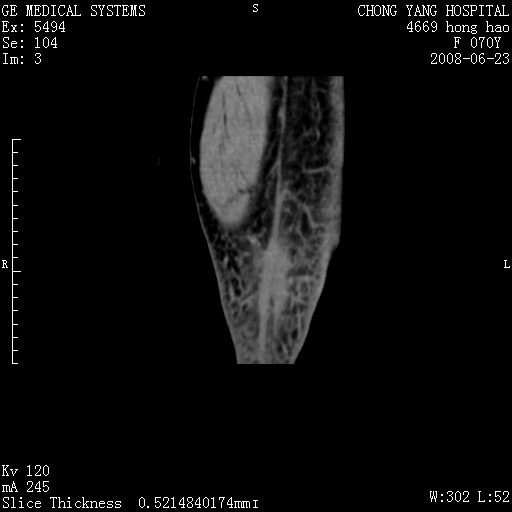

以下是引用peijunlong在2008-6-24 20:56:00的发言:[br]左小腿后方软组织皮下脂肪间隙见条片状密度增高影,范围较大,相邻皮下见条索影。[br]考虑:无菌性炎症可能性大[br]鉴别:主要与蔓状血管瘤鉴别,蔓状血管瘤也可表现为软组织内葡伏生长的扁平状的软组织密度影,但它的范围更大,且主要在软组织内,肌间隙中,皮下脂肪间隙内罕见。